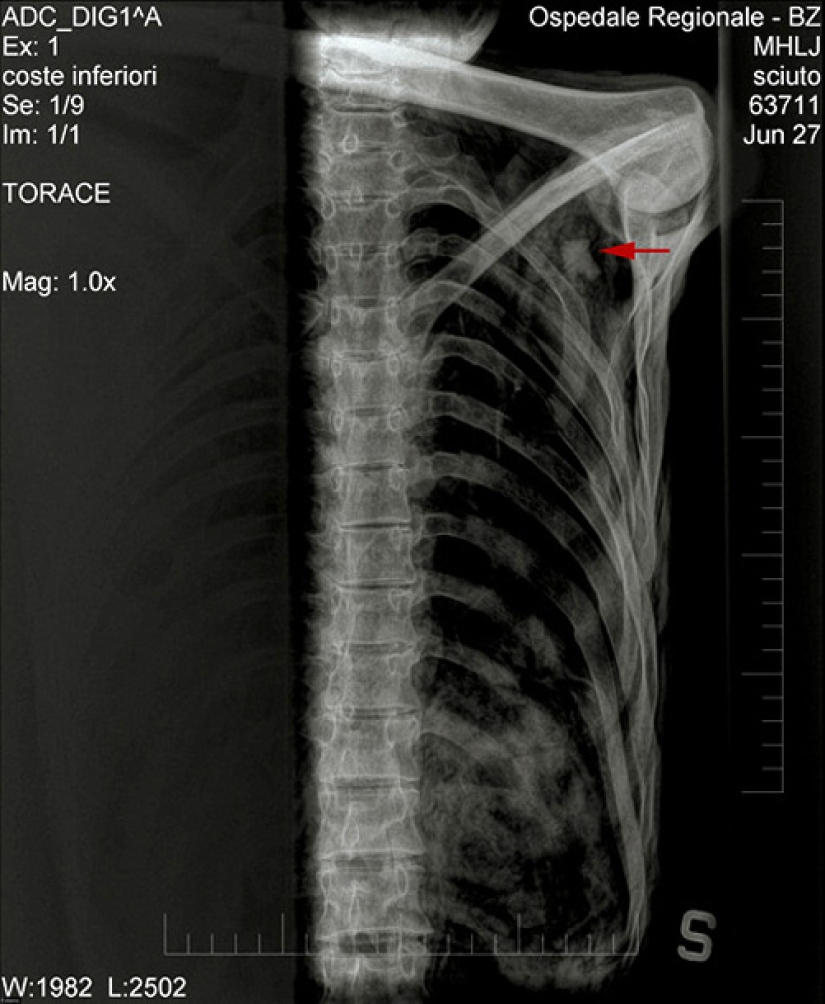

Dr. Edward Egarter Wigl and his colleagues are studying an arrowhead stuck in the shoulder of Etzi. Someone shot Etzi in the back more than five thousand years ago, the arrow pierced so deeply into the shoulder that it was not possible to get the tip of Etzi.

The red arrow on the X-ray image marks the location of the arrowhead.